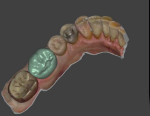

In this case, the preparation, margins, and occlusal reduction were all deemed clinically acceptable, so the scan was saved as a stereolithography (STL) file and uploaded to the manufacturer's cloud site directly from the acquisition unit. Next, the file was downloaded to the design computer, and the design software (DentalCAD, exocad) was used to create the prosthesis in a series of steps that started with the margins and ended with a completed crown (Figure 10 and Figure 11). Once past a brief learning curve, users can digitally design a prosthesis in approximately 10 minutes. The completed prosthetic design was then saved and opened in the chairside mill's software application (VPanel for DWX, Roland DGA). This software takes the digital design and translates it into a format that can be used by the mill to create the physical restoration. It also monitors the milling process and tracks bur life as well as indicates when routine maintenance is required.